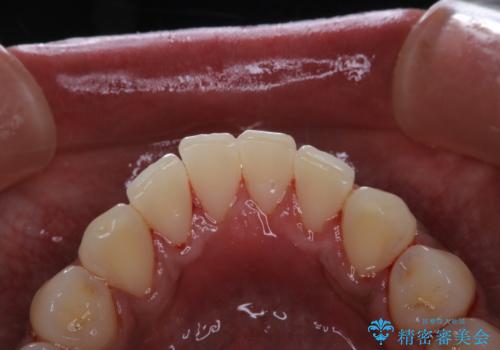

歯についたタバコのヤニをPMTCで綺麗に

- 電子タバコを吸う習慣があり、ステインがついてしまっている見た目が気になるとのことで来院されました。ステインだけではなく、歯石も全体的に付着していたためPMTC60分コースを行いました。